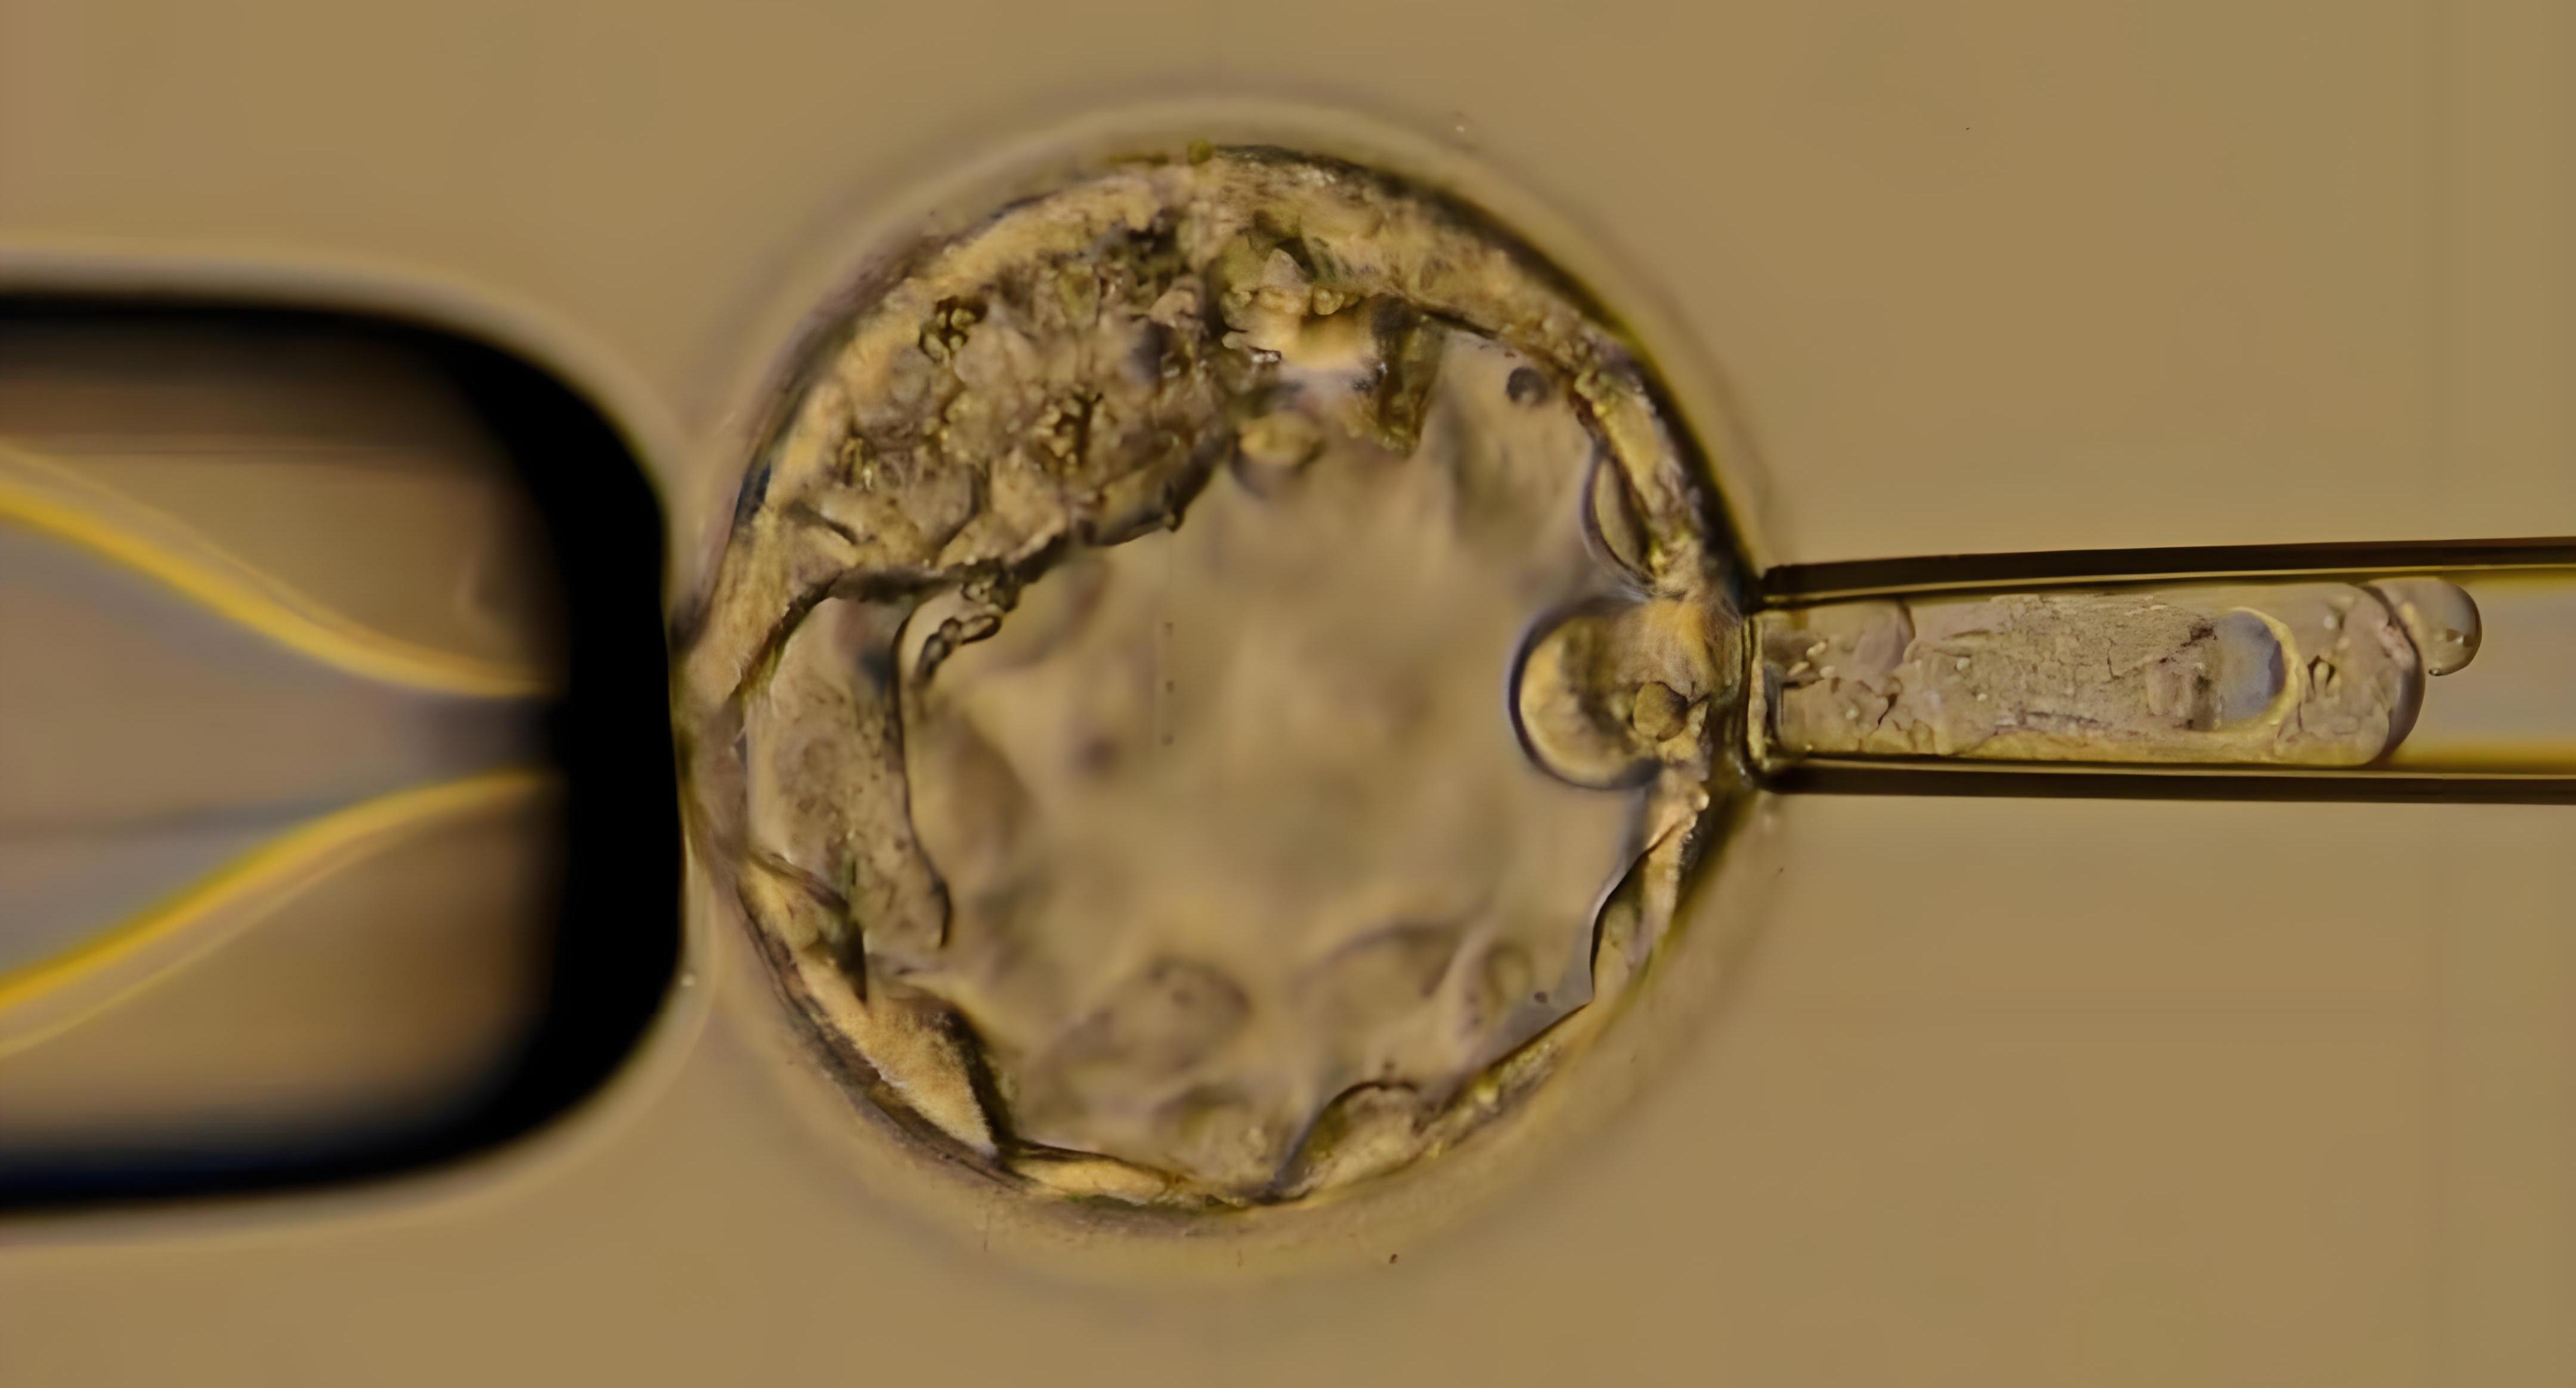

泰国第三代试管技术为基因疾病携带家庭带来了福音。其核心技术原理是在体外受精的基础上,对胚胎进行遗传学检测。在胚胎发育到一定阶段时,取少量细胞进行基因分析,检测是否存在致病基因或染色体异常,从而筛选出健康的胚胎进行移植。

助孕流程严谨且科学。其先,夫妻双方需要进行全面的身体检查,包括基因检测,以明确致病基因和身体状况。然后,医生会根据检查结果制定个性化的促排卵方案,通过药物刺激卵巢,获取多个卵子。接着,在实验室中,将卵子与精子进行体外受精,培养成胚胎。当胚胎发育到囊胚阶段时,进行胚胎活检,提取细胞进行遗传学检测。经过一段时间的等待,检测结果出来后,选择健康的胚胎移植到调理好的母体子宫内。之后,进行黄体支持,等待胚胎着床和妊娠。